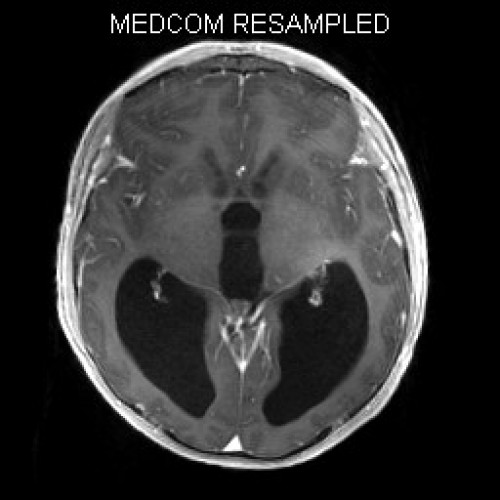

ICD: C75.3

ICD: G91.9

12-jähriger Junge. Die Eltern werden zu einem Gespräch bei der Klassenlehrerin gebeten, weil ihr Sohn sehr unaufmerksam geworden sei und seine Leistungen in der Schule bedenklich abgenommen hätten. Er droht das Klassenziel der 6. Klasse nicht zu erreichen.

Den Eltern war seit längerer Zeit bereits aufgefallen, dass sich ihr Sohn nach der Schule am liebsten ins Bett lege, um für eine Stunde einen Mittagsschlaf zu halten.